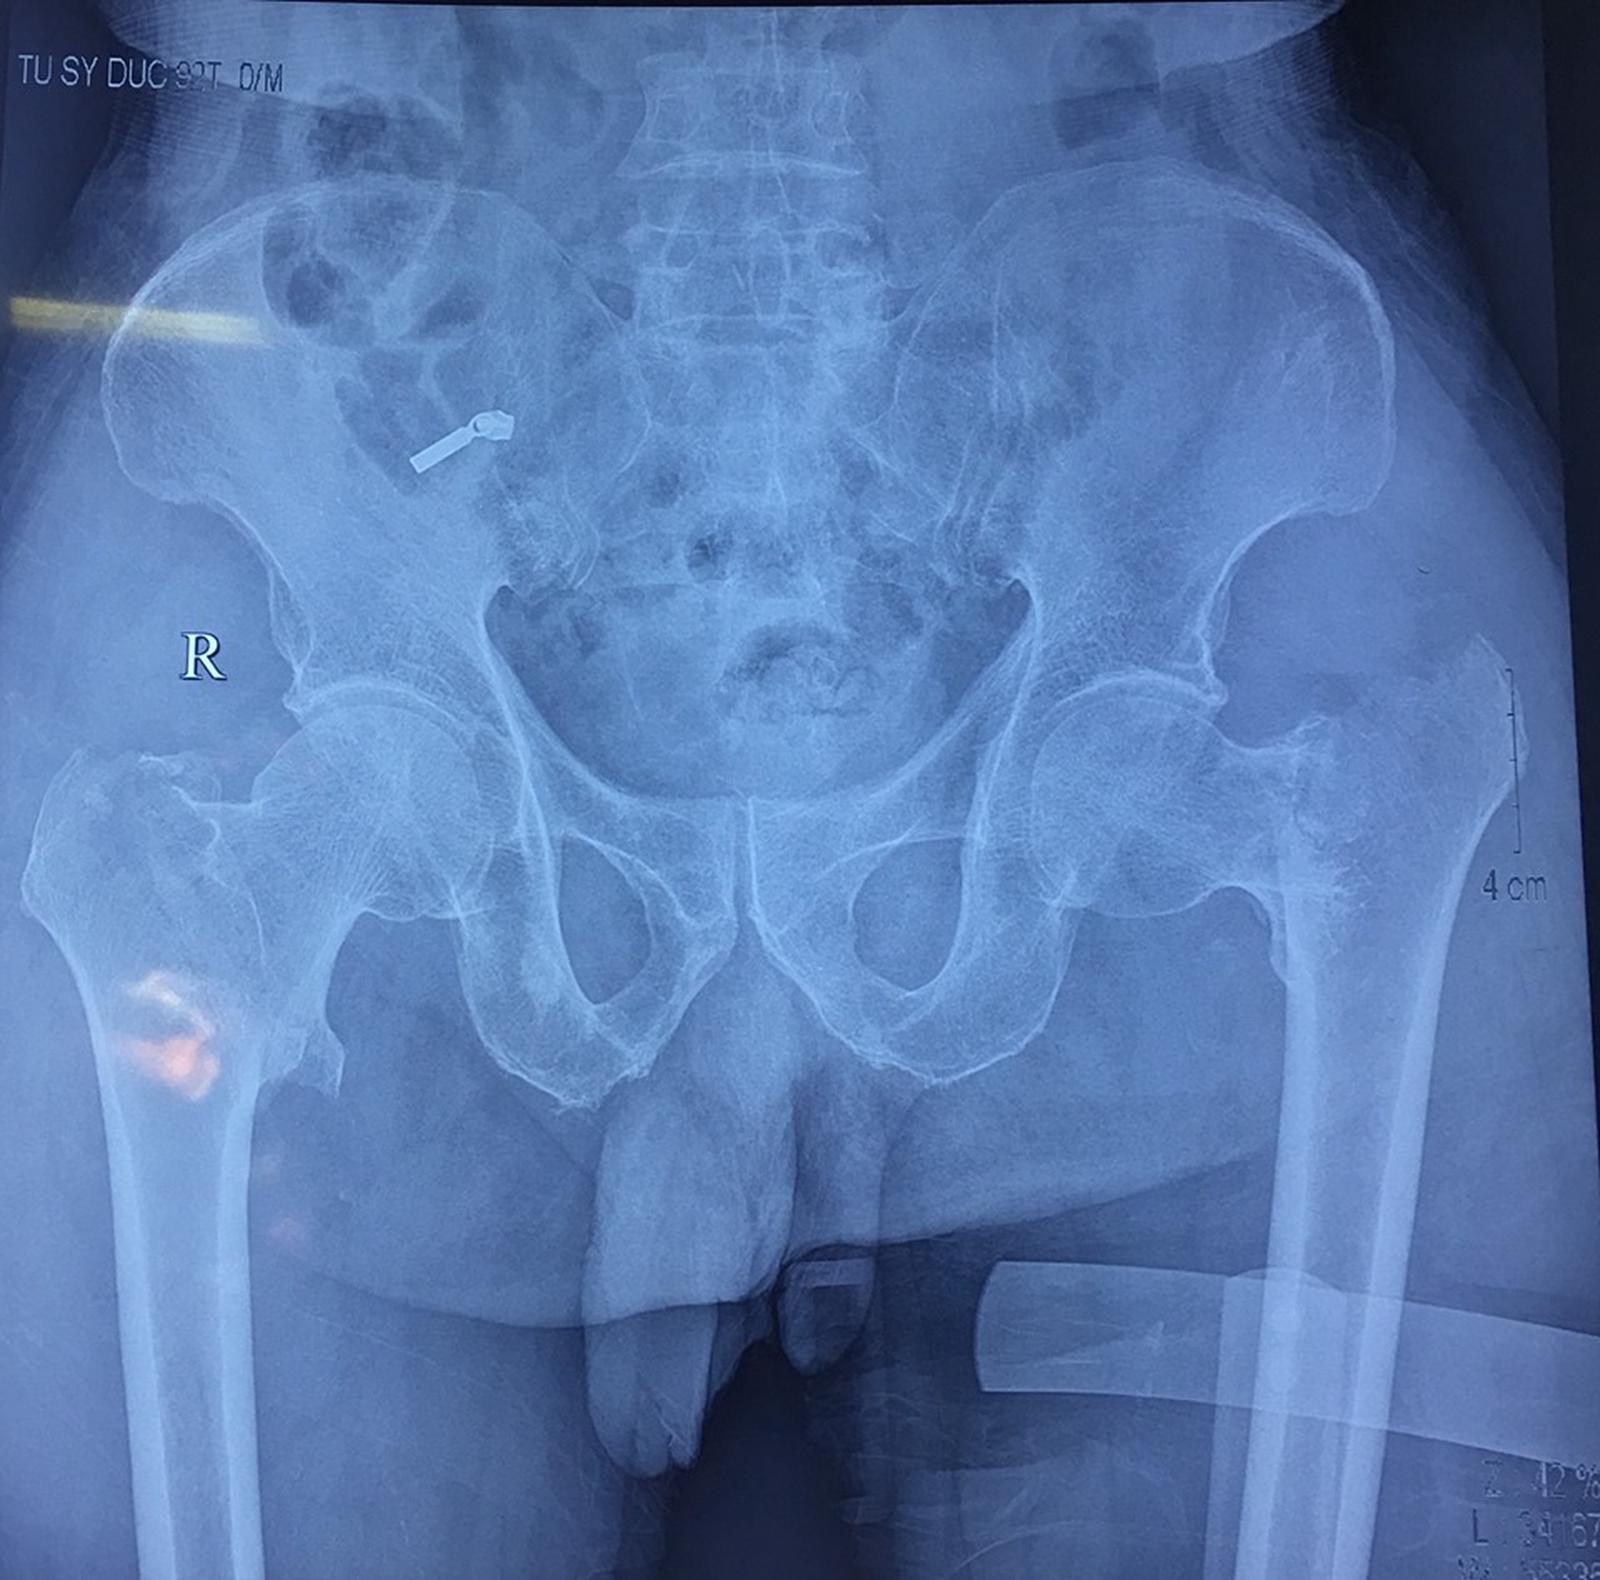

Hình ảnh chụp X quang của bệnh nhân

(Thanh tra)- PGS.TS Nguyễn Mạnh Khánh - Phó Viện trưởng Viện Chấn thương chỉnh hình, Bệnh viện Hữu nghị Việt Đức cho biết, các bác sĩ vừa tiến hành phẫu thuật cùng một lúc thay khớp háng 2 bên cho cụ ông đã 92 tuổi, do tai nạn sinh hoạt, bị ngã và gãy cổ xương đùi cả hai bên. Đây là lần đầu tiên các bác sĩ phẫu thuật cho bệnh nhân đồng thời cả 2 bên khớp háng.

Đây là một trường hợp hiếm gặp. Trên thế giới, y văn cũng cực kỳ hiếm gặp. Cổ xương đùi là phần yếu nhất của khớp háng, chịu lực chính cho trọng lượng cơ thể, thông thường người bệnh bị gãy 1 bên khớp háng. Gãy 1 bên khớp háng đã là tổn thương rất nặng nề, đặc biệt lại là đối với người già, trường hợp này người già trên 92 tuổi, gãy đồng thời cả hai bên khớp háng.